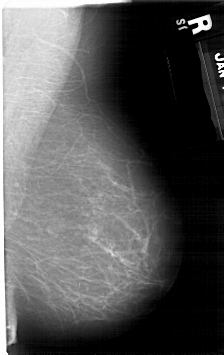

A_1271_1.RIGHT_MLO

RIGHT_MLO LINES 5311 PIXELS_PER_LINE 3346 BITS_PER_PIXEL 12 RESOLUTION 43.5 NON_OVERLAY